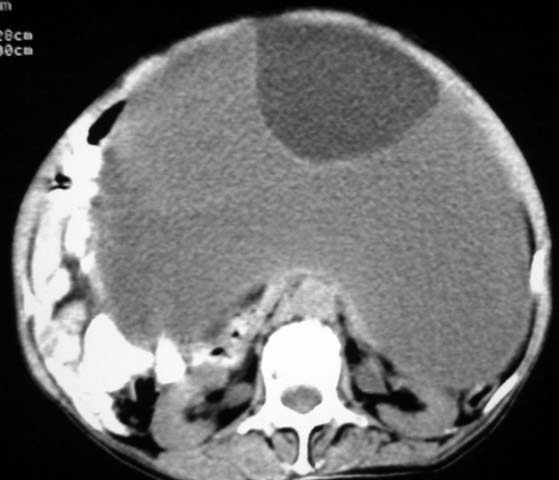

女,75岁,腹部胀大半年余,无其他症状。

考虑来源与卵巢的巨大囊腺瘤或囊肿。

真是腹大如牛,考虑卵巢巨大囊腺瘤或囊肿。

考虑来源卵巢巨大黏液性囊腺瘤。